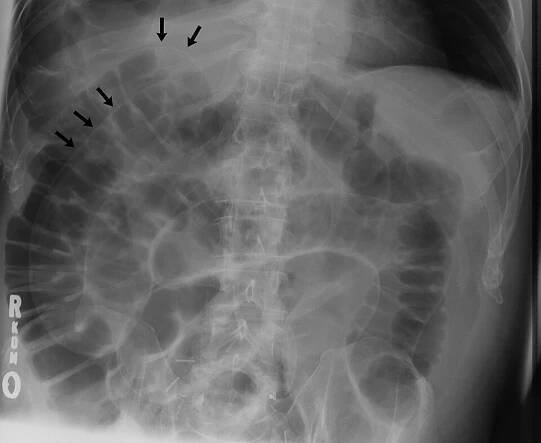

Double wall sign. This is a secondary sign of pneumoperitoneum. Patient is supine, and air within the abdomen and lumen of the bowel accentuate both sides of the bowel wall.

Spontaneous Intestinal Perforation | Applied Radiology

Pneumoperitoneum je stav, kterým označujeme přítomnost volného vzduchu, resp. plynu v dutině břišní. Diferenciální diagnostika příčiny vzniku pneumoperitonea je poměrně široká a představuje různý stupeň závažnosti.